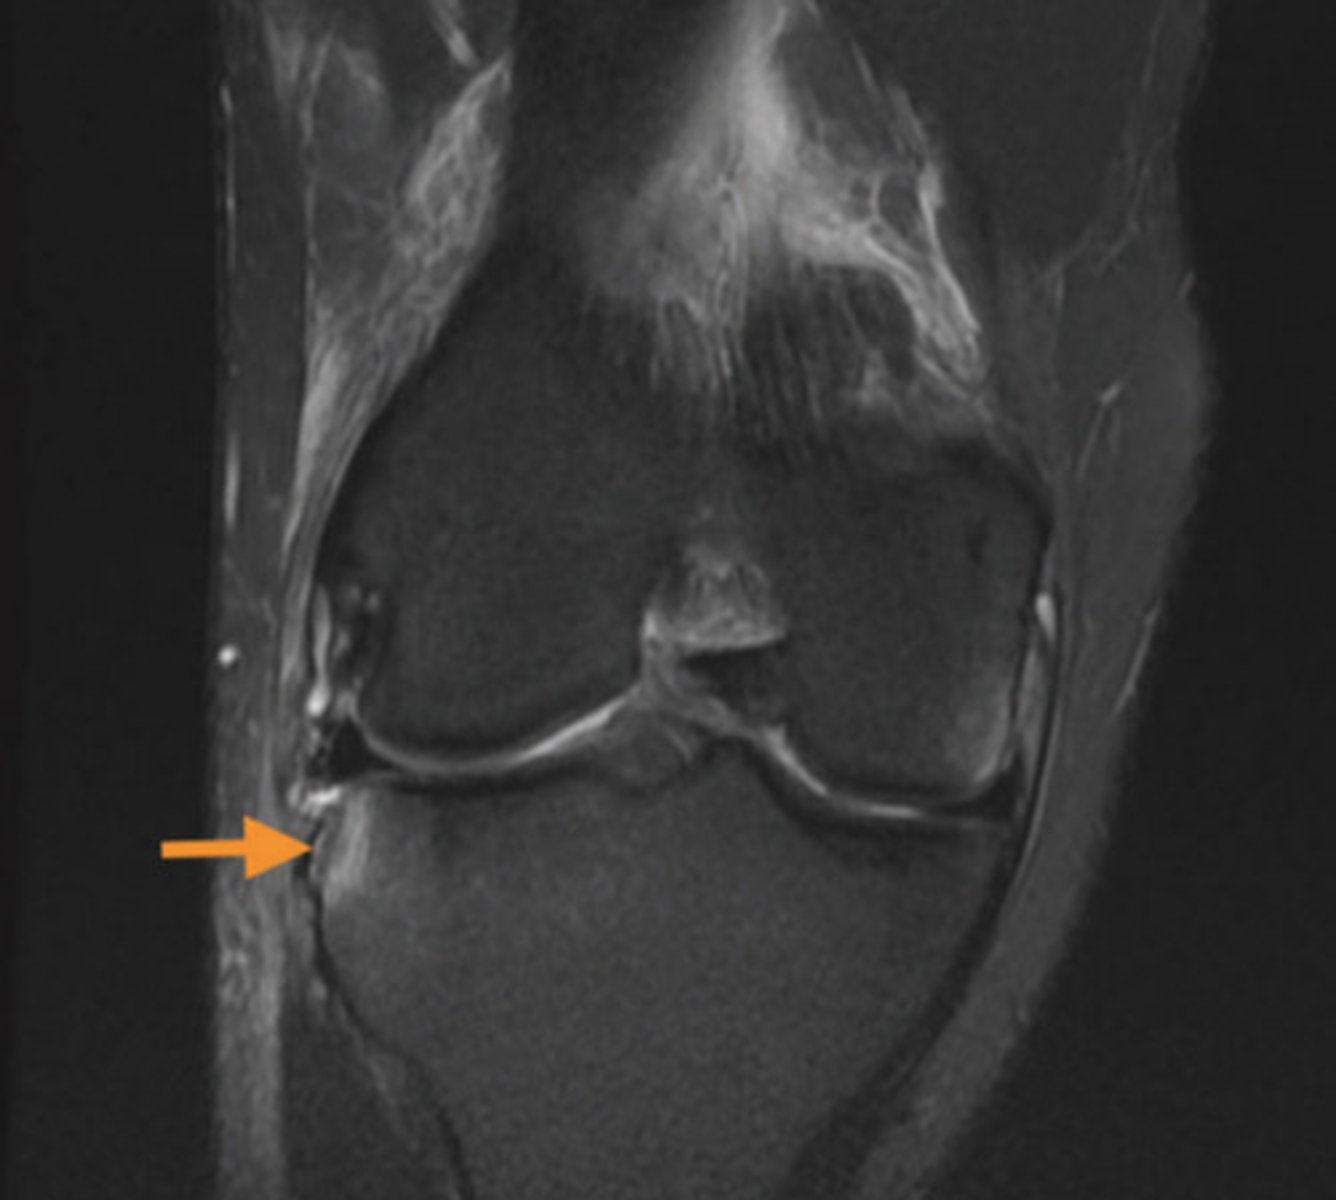

identify the view of this MRI

coronal view

what structure is indicated by the orange arrow?

lateral meniscus, posterior horn